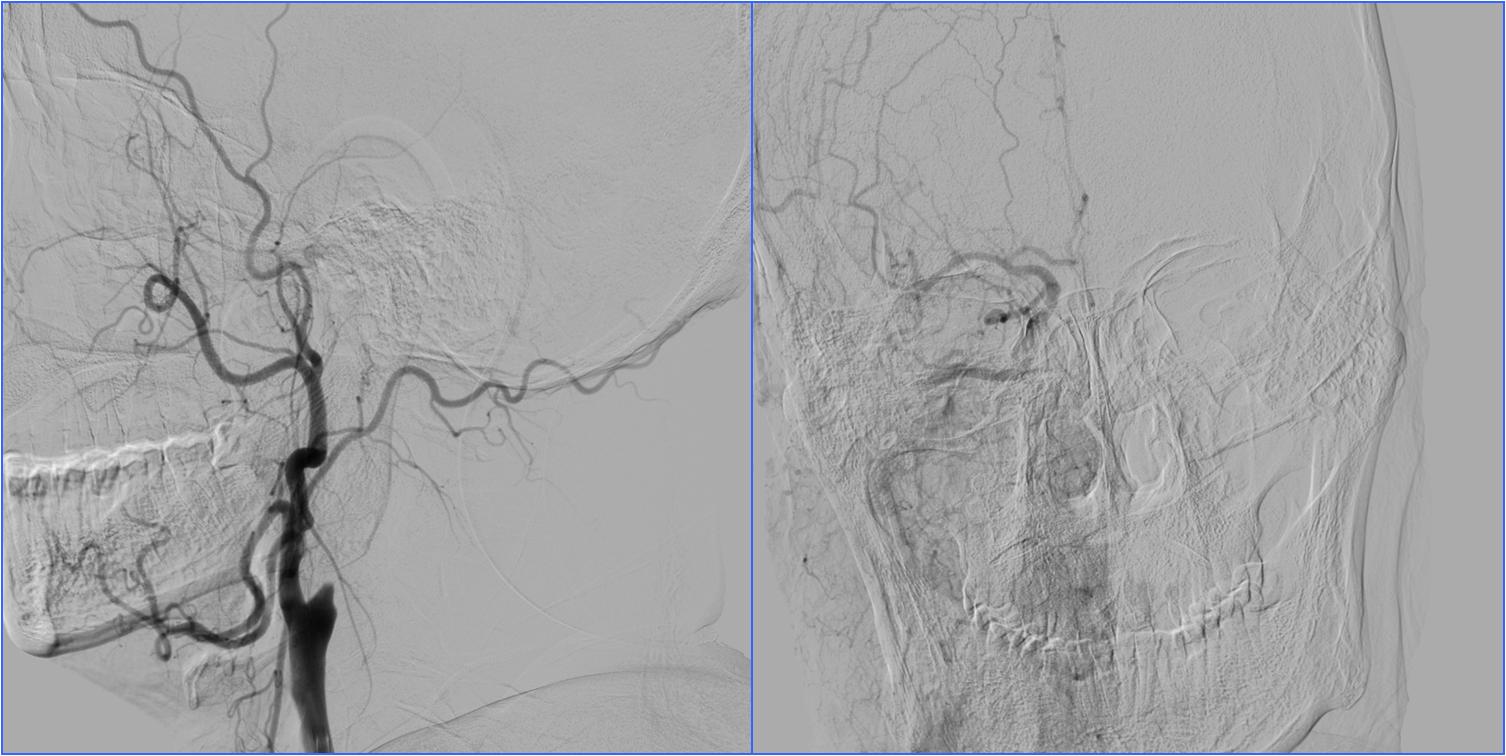

▼左侧大脑中动脉高密度征

▼气管插管时机:释放支架重建血流后

术前静脉溶栓

术中动脉溶栓

心源性栓塞出血转化

Case1 全麻插管时机选择

》男,60岁。有房颤史。

》7:50三次TIA(发作性右侧肢体无力),8:45到我院急诊,8:52完成头CT检查。

》9:30再次加重,11:30通知介入医师。

》NIHSS评分10分。

》12:20股动脉穿刺。

》12:50血管再通。

》10天后出院,NIHSS 0分。

》全身麻醉。